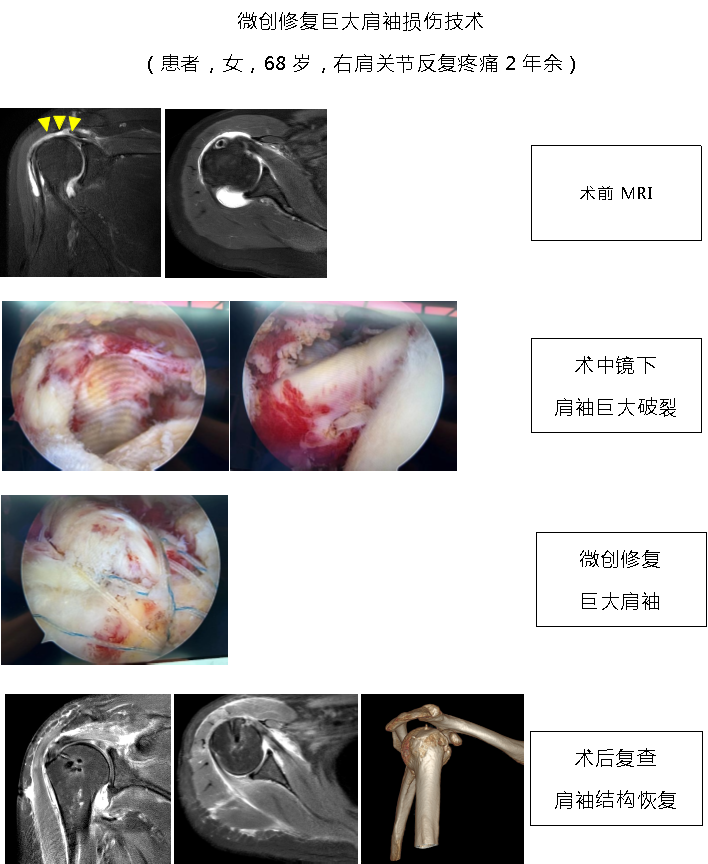

1.国际前沿的微创诊疗技术体系:科室聚焦肩、肘、髋、膝、踝多关节运动损伤,以 “精准化、个体化” 为核心,突破多项关键技术。膝关节领域:建立分龄化治疗方案 —— 青少年 “骨骺保护型前交叉韧带重建” 规避生长发育风险,成人 “联合前外侧韧带加强术” 提升术后稳定性,技术成熟度获行业广泛认可; 肩关节领域:个性化修复肩关节盂唇损伤、肩袖损伤,助力患者回归正常生活、重返运动;髋关节领域:为国内较早开展 “由外到内入路” 髋关节镜技术的科室之一,显著提升手术视野清晰度与操作安全性,年手术量超 300 台,居广东省前列。

3.核心业务范围:科室覆盖多关节运动损伤微创诊疗,主要包括:膝关节:前后交叉韧带重建、多韧带重建、半月板成形 / 修补 / 移植、髌股关节稳定术、关节软骨移植与修补、关节内游离体摘除;肩关节:肩袖撕裂关节镜下修补术、肩关节不稳关节镜下修复术(含 Laterjet 手术)、冻结肩关节镜下松解术、肩峰关节镜下减压成形术、SLAP 损伤修补术、肱二头肌腱固定术;髋关节:盂唇修补、股髋撞击症微创治疗、关节内游离体摘除;踝关节:踝关节不稳矫正、踝关节骨软骨损伤微创及开放治疗、跟腱腱病和断裂的微创及开放治疗、关节镜下各类踝关节疾病的微创治疗;肘关节:肘关节清理、网球肘、肘关节不稳、韧带重建;肘关节:腕关节清理、腕关节三角软骨损伤、腕关节不稳。